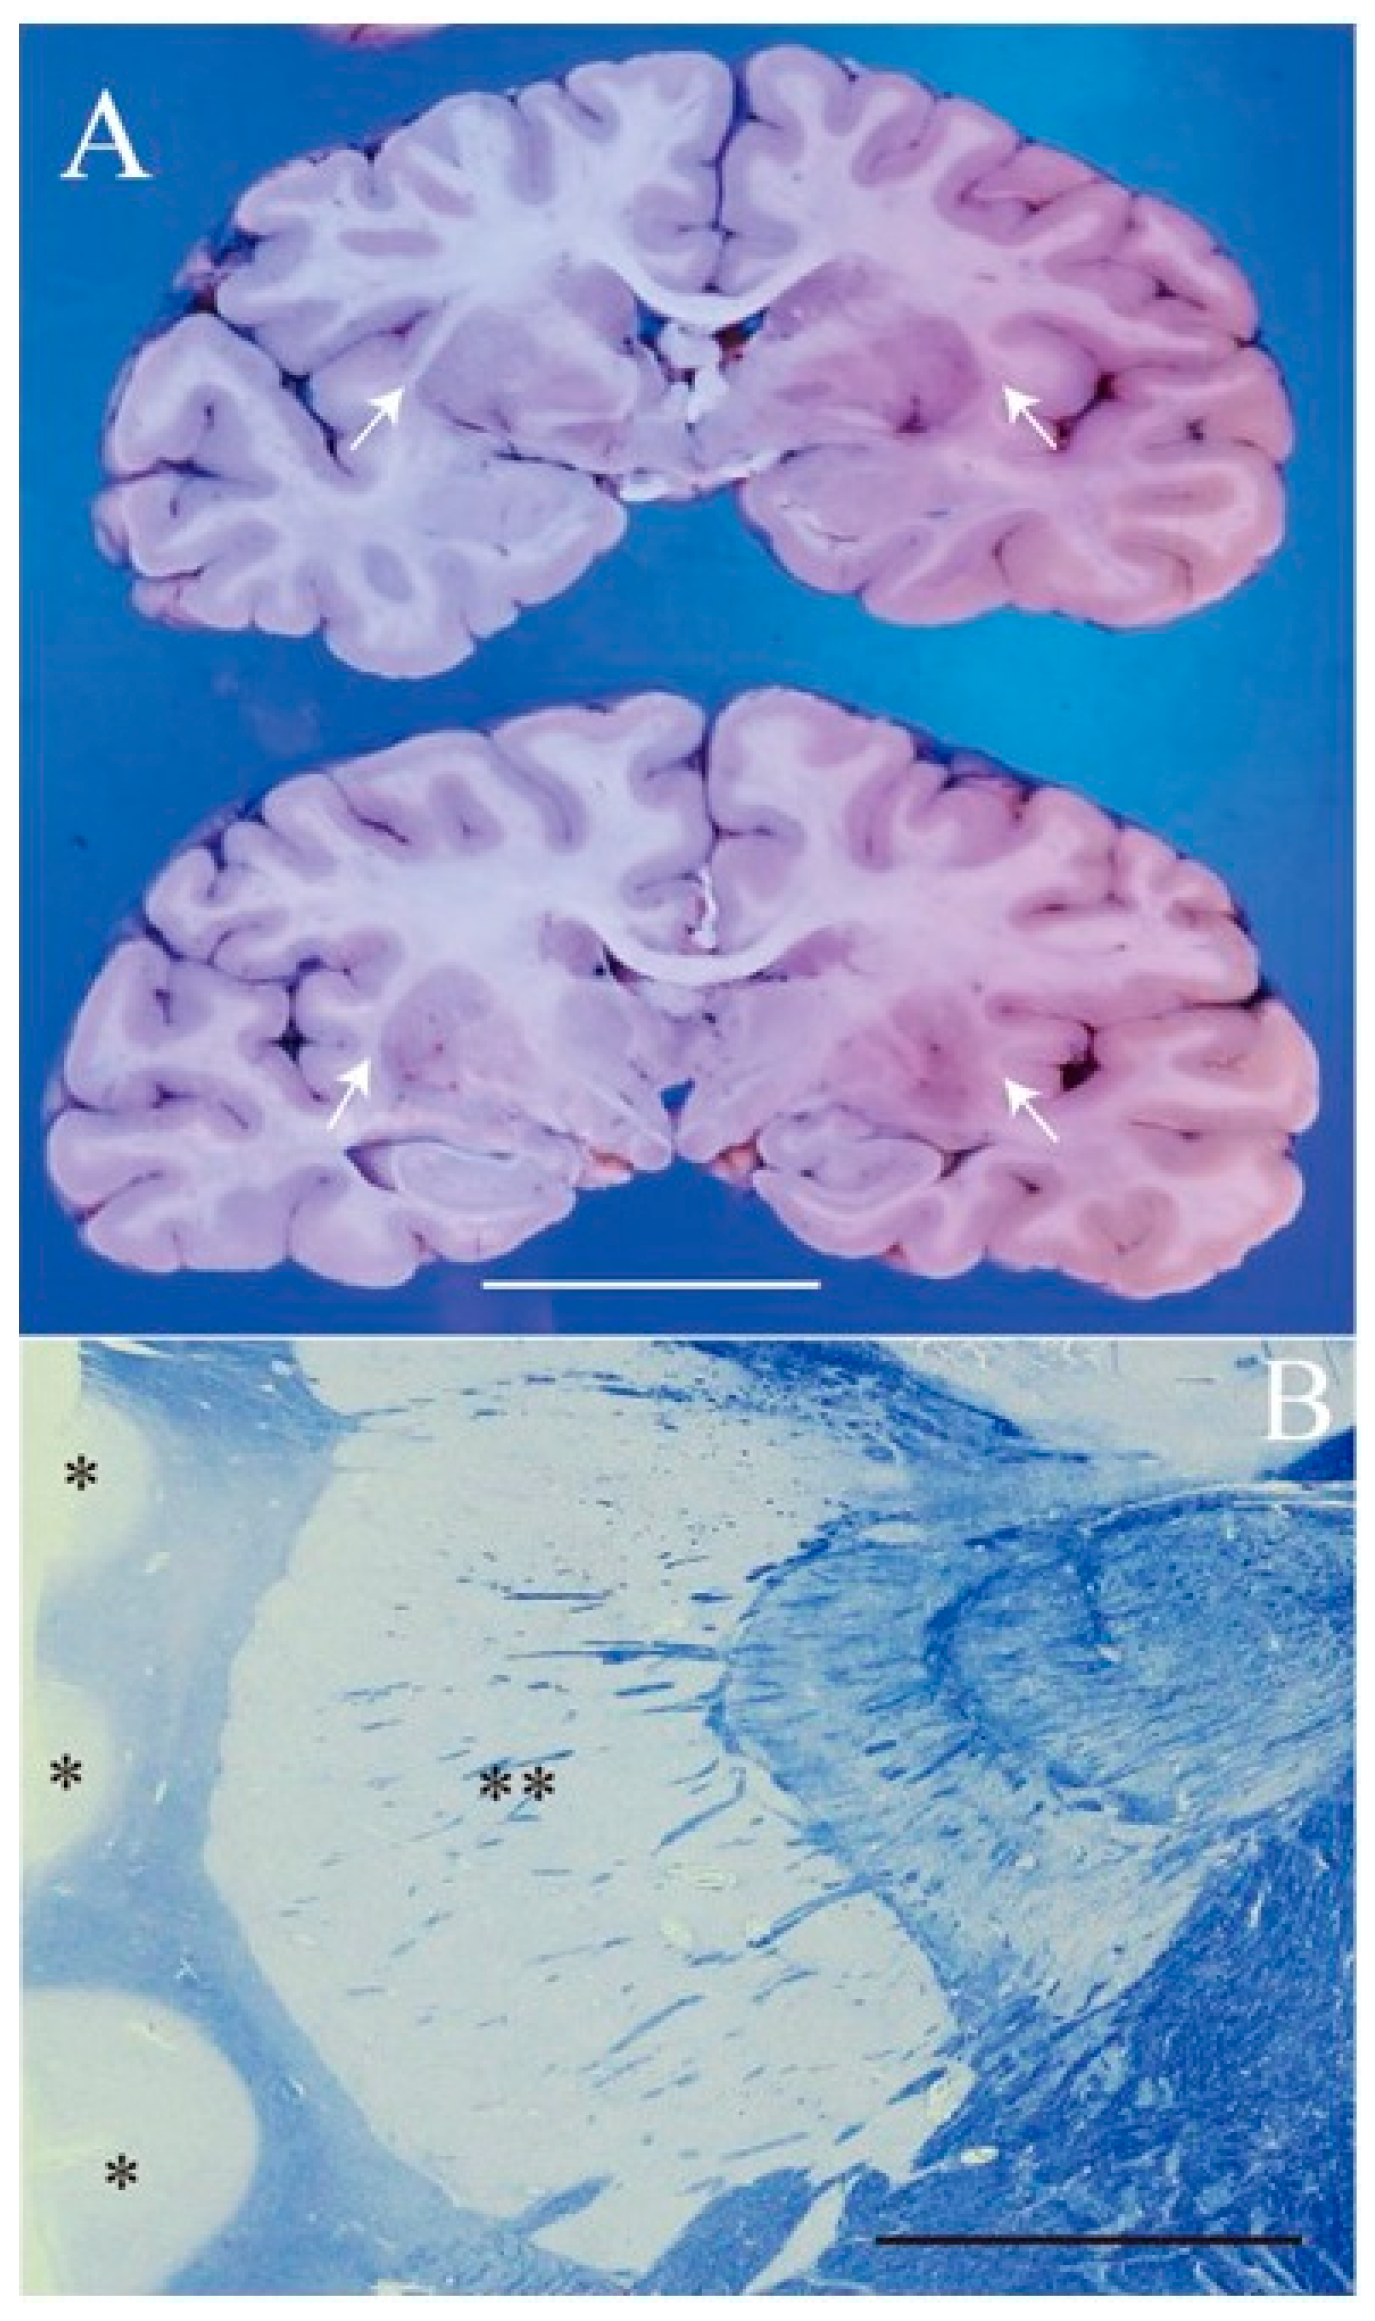

2. Case Presentation